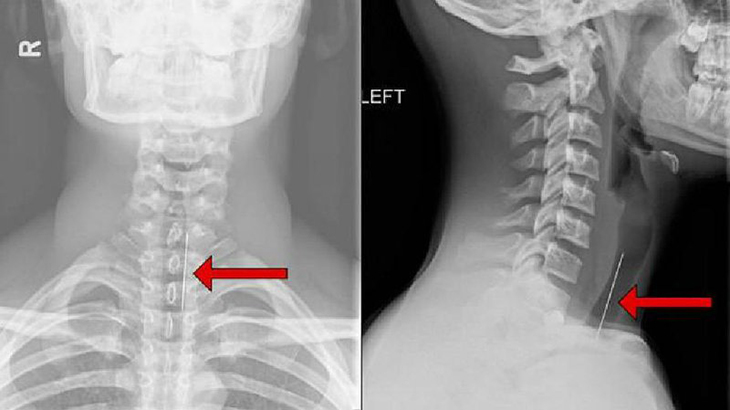

Chụp Xquang có thể thấy hình ảnh tổn thương lao điển hình là đĩa đệm hẹp lại và ở giai đoạn muộn các thận đốt sống dính sát lại với nhau, bờ thân đốt sống phía trên và dưới đĩa đệm bị phá hủy tạo hang lao, thân đốt sống bị xẹp, nhất là ở phía trước làm cho đốt sống có hình chêm và cột sống bị gù, mỏng gai của đốt sống đó lồi ra phía sau.

Nếu có ổ áp-xe lạnh thì trên phim Xquang sẽ thấy bóng mờ của túi áp-xe lạnh. Hình ảnh Xquang của lao cột sống khác với tổn thương ung thư như sau: trong ung thư tổn thương chủ yếu ở đốt sống, đĩa đệm không bị tổn thương, vì vậy không thấy xẹp đĩa đệm và dính các đốt sống.

bệnh lao cột sống Người bệnh nên chụp X-quang để có thể chẩn đoán chính xác bệnh lao cột sống